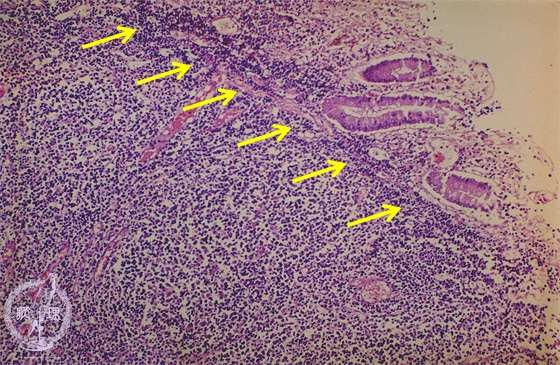

- ★(9)Malignant lymphoma of the stomach (MALT lymphoma)

Microscopic view (H&E stain, intermediate power): The mucosa is displaced due to proliferation of atypical lymphocytes.